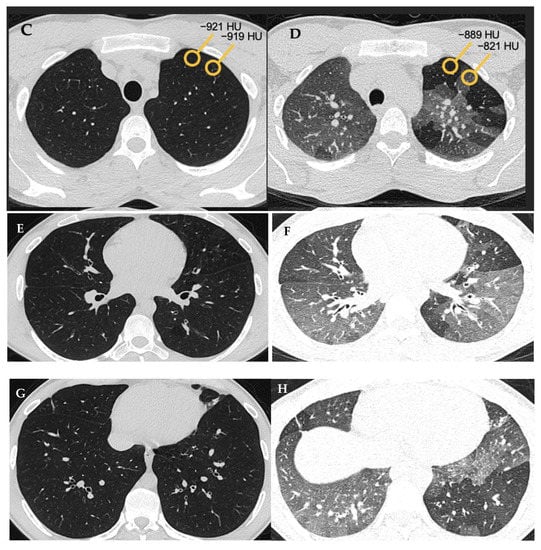

“Mosaic attenuation” is a term reserved for inspiratory phase CT. It is defined as sharply demarcated areas of low and high attenuation. Mosaic attenuation can be seen in vascular diseases, airway diseases, or infiltrative diseases [35] (Figure 2 and Figure 3). As opposed to mosaic attenuation, the term “air trapping” is only used on expiratory phase CT (Figure 2, Figure 3 and Figure 4). This term represents abnormal air retention distal to airway obstruction and manifests as areas of lucent lung on a background of normal relatively high attenuation lung parenchyma on expiratory imaging [3]. Like mosaic attenuation, the term “mosaic perfusion” (Figure 5) is also reserved for inspiratory CT. In mosaic perfusion abnormality, one may see a smaller caliber of the pulmonary vasculature within areas of low attenuation compared to normal vessel caliber in areas of higher attenuation. However, mosaic perfusion can be seen because of a vascular disease (pure perfusion abnormality), or in airway diseases where there is mosaic perfusion secondary to abnormal ventilation. Hence, the role of expiratory CT to aid differentiation of mosaic perfusion is secondary to vascular diseases from airway disease. If there is a similar gradient of attenuation between low and high attenuation areas on inspiratory and expiratory scans, mosaic perfusion is secondary to a vascular disease. If a higher attenuation gradient is measured on expiratory scans, an airway disease is the likely cause of mosaic perfusion [36].

Figure 4. Air trapping (A,B). Axial inspiratory (A,C,E,G) and expiratory phase (B,D,F,H) CTs. On expiratory images the normal lung shows increase in the parenchymal density and decrease in volume. Interspersed geographic areas of air trapping lack the expected increase in density and volume reduction. Accentuated attenuation difference between areas of low and high density (32 versus 98 HU on image (C) and (D) respectively) indicates airway disease.

Given the fact that most people do not relate to the “headcheese” sign [37], the term “three-density pattern” (Figure 6 and Figure 7) is now a favored terminology. This term is used when there is both an obstructive and infiltrative process in addition to areas of normal lung parenchyma manifesting as clearly delineated zones with three different attenuations [38]. The manifestations of obstructive abnormalities are areas of decreased attenuation and decreased vascularity with no significant increase in attenuation on expiratory scans. Areas with an infiltrative disorder manifest as GGO or even consolidative opacities with increase in attenuation on expiratory scans. Areas of interposed normal lung present as demarcated normal lungs with expected increased attenuation on expiratory scans. Three-density pattern is specific for fibrotic HP [3,39].